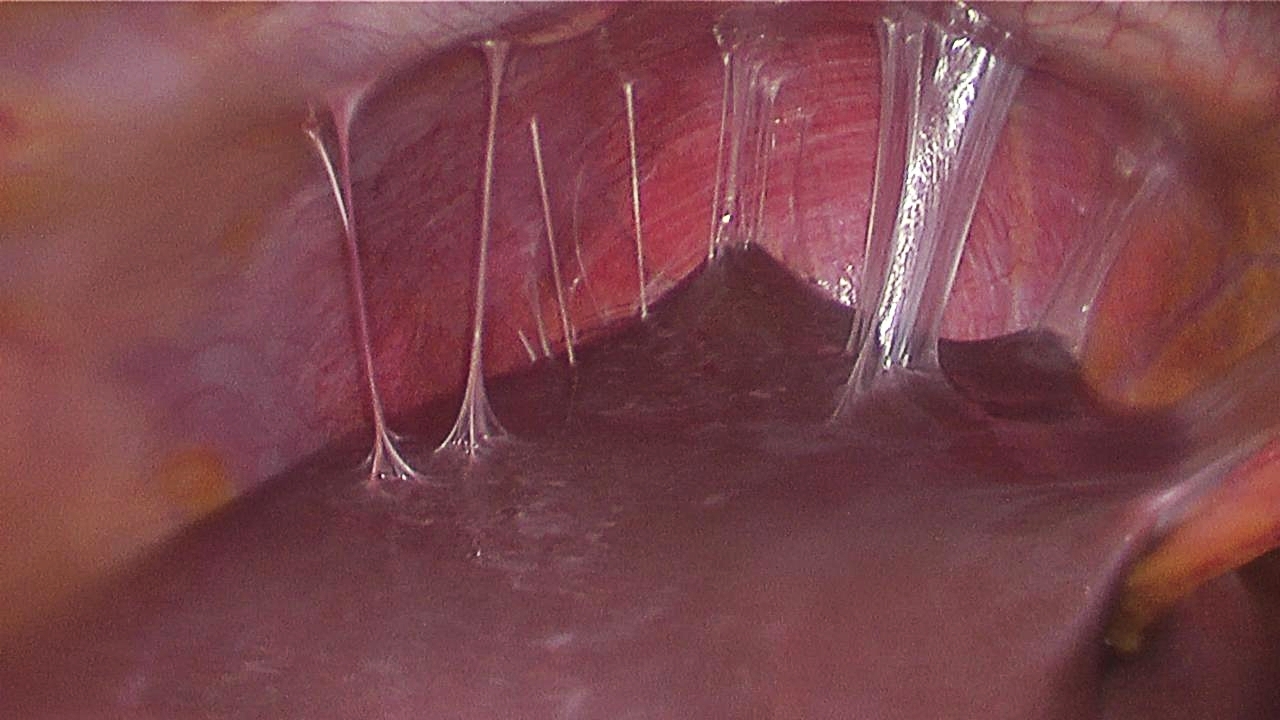

Fitz-hugh-curtis (perihepatitis)

infection and inflammation of liver capsule and “violin string” adhesions of peritoneum to liver